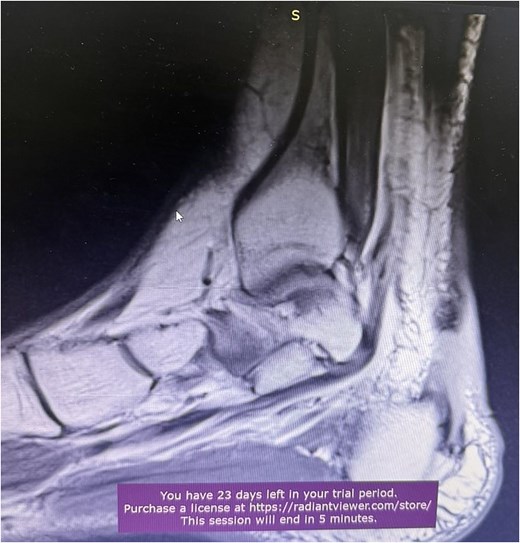

A 68-year-old female presented to the emergency department with significant discomfort localized to the Achilles tendon region. Her medical history was relatively uneventful, except for hypothyroidism and a previous diagnosis of Achilles tendinopathy (Fig. 1), that was treated conservatively with ten daily sessions of percussive ultrasound therapy. More specifically radial extracorporeal shockwave therapy (ESWT) was used, with 2.000 shockwaves at 12 Hz, which was followed by physical therapy exercises and ice therapy. Following the therapeutic sessions, the patient experienced acute symptoms, including a pronounced popping sensation and significant functional impairments.

A comprehensive physical examination provided significant insights into the patient’s condition following the Achilles tendon rupture. The Thompson test was particularly noteworthy, showing an absence of plantar flexion upon calf compression, strongly indicating a complete tendon rupture. The examination further revealed a palpable gap in the Achilles tendon and increased passive dorsiflexion. Symptoms included significant weakness, difficulty walking and heel pain. Imaging studies, including X-rays (Fig. 2) and magnetic resonance imaging (MRI) (Fig. 3), confirmed these findings, showing an acute rupture with retracted tendon edges, distinguishing it from chronic condition and suggesting a possible link to the vigorous ultrasound therapy [3].